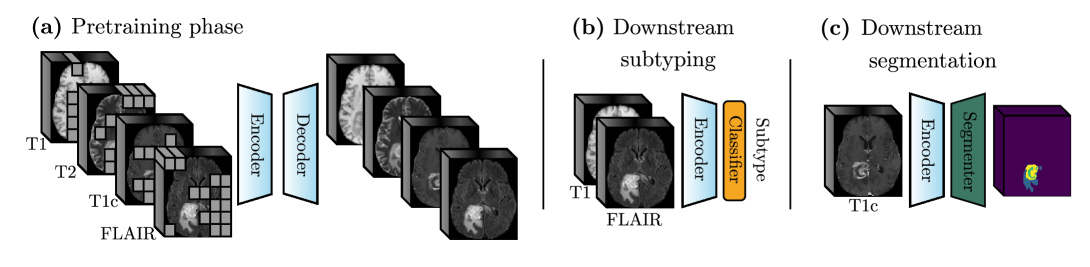

Figure 1: (a) BM-MAE pre-training on all modalities through the reconstruction of masked patches. The trained encoder can handle any modality combination. (b) Fine-tuning the encoder for subtyping on T1 and FLAIR. (c) Fine-tuning the same encoder for segmentation on T1c.

Inspired by the growing popularity of Multimodal MAEs in computer vision [19, 20, 21], we introduce Brain Multimodal MAE (BM-MAE) to address these aforementioned challenges. BM-MAE is a scalable, attention-based pre-training strategy designed to learn rich cross-modal representations while efficiently handling the complexity of high-dimensional 3D multimodal data. A unique Vision Transformer (ViT) encoder [22] is first pre-trained on multimodal data through masked image modeling, where large portions of the input are masked and the model learns to reconstruct them. After the pre-training phase, the encoder can be adapted to any modality combinations and be fine-tuned on diverse downstream tasks, as illustrated in Figure 1. To the best of our knowledge, this is also the first work proposing to handle missing modalities in multimodal brain MRI using a single shared ViT. To thoroughly assess the effectiveness and flexibility of our pre-training strategy, we conduct a comprehensive set of experiments across multiple clinical tasks and modality configurations. Hence, first an encoder is pre-trained on the BraTS2021 [23] dataset using all four anatomical modalities. Then, this same encoder is fine-tuned across every modality combinations for various downstream tasks including glioma segmentation, glioma subtyping and survival prediction. Across all evaluated tasks and modality configurations, fine-tuning the pre-trained encoder consistently leads to strong and reliable performance, demonstrating both its flexibility and robustness.